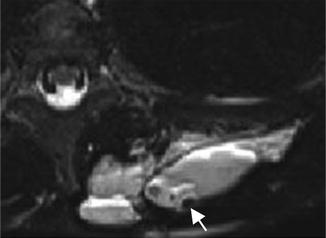

Glomus tumor of the nail bed. Axial T2-weighted MR image with fat suppression shows a 2 mm markedly hyperintense lesion of the nail bed